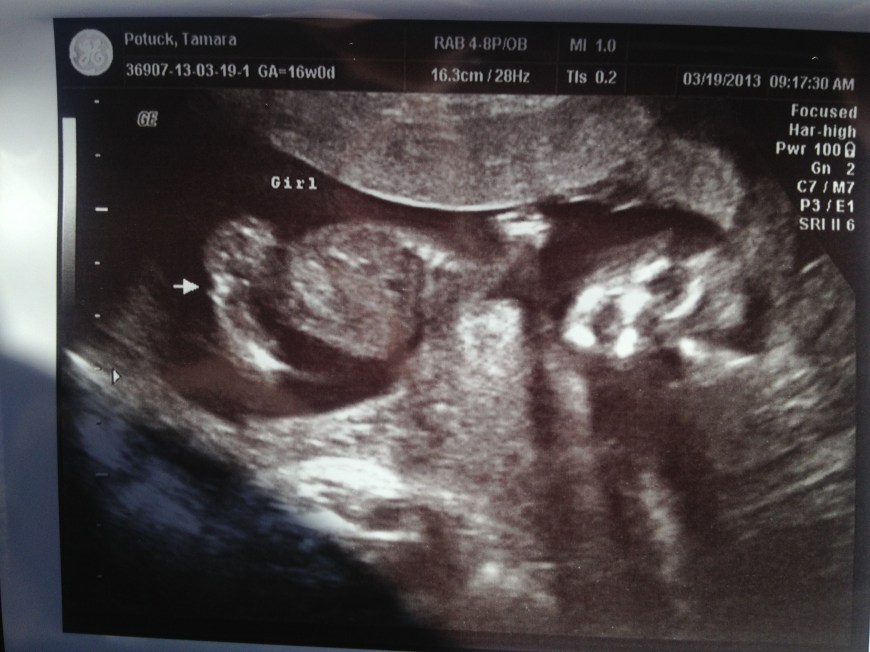

It’s a WHAT!?!?!

Can you tell from the photos what gender baby Potuck is? Frankie and Bruce got super excited and decided to dress the part 😉

YEP! We’re adding a girly vibe to our tribe! IT’S A GIRL!!!!!!!!!

Our little baby girl!